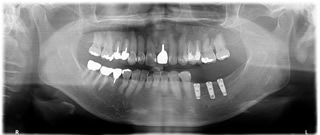

インプラント治療例2

• 1)平成26年11月21日 初診 64歳女性

右下の歯(矢印の歯)他院で抜いたほうがいいと言われ相談に来院。過去に3本他院にてインプラント経験あり。当医院でCT撮影をしたところはっきり歯牙に破折が起きており抜歯が必要と判断しました。

• 2)患者様もCT画像を見て納得されて当院でのインプラントを希望されました。抜歯後、歯肉が治るのを待ってインプラントを埋入しました。

• 3)平成27年6月2日 右下 旧インプラントと連結して上部構造をセットました。